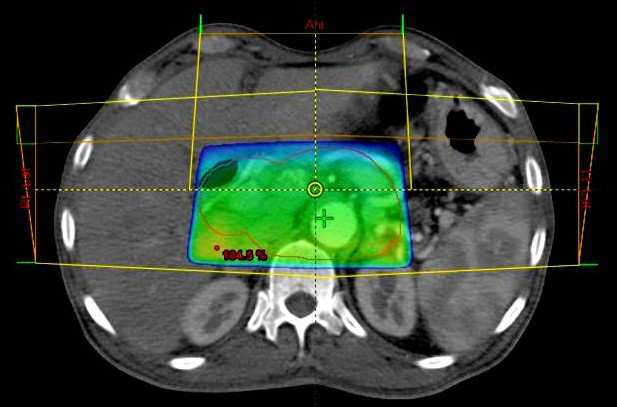

Σύμμορφη Τρισδιάστατη Ακτινοθεραπεία 3DSRT

Η σύμμορφη τρισδιάστατη ακτινοθεραπεία (3D Conformal Radiotherapy - 3DCRT) επιτυγχάνει να προσαρμόσει την περιοχή υψηλής δόσης στον ακριβώς καθορισμένο όγκο - στόχο, περιορίζοντας ταυτόχρονα τη δόση στους παρακείμενους υγιείς ιστούς.

Στην τεχνική αυτή χρησιμοποιούνται πολλαπλά πεδία ακτινοβολίας ομοιόμορφης έντασης το σχήμα των οποίων είναι τέτοιο που προσαρμόζεται στον όγκο.